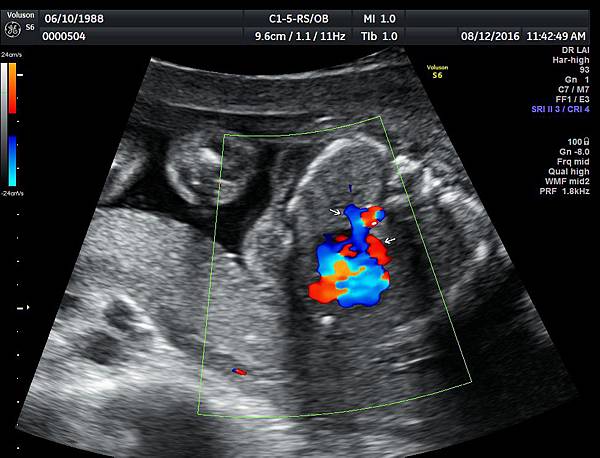

我看肺靜脈的心路歷程可以分成三個階段,第一個階段是用gray scale(黑白)看到左右肺靜脈下行支回到左心房(附圖 1.2.),第二個階段是用flow(彩色)看到左右肺靜脈回到左心房(附圖 3.4.),第三階段是同時要看到黑白和彩色的左右肺靜脈回到左心房,為什麼只有看flow(彩色)不安全呢?因為右肺靜脈的flow有時候是假影,為何會看到假影?因為右心房到左心房的flow overlapping(重疊)造成的(附圖 5.),如何判斷是假影,只要關掉flow看黑白的即可證明右肺靜脈沒有進入左心房(附圖 6.)。

如果同時看到左右肺靜脈進入左心房,這種誤判的機率下降很多,如果只能看到一條肺靜脈的血流,我會選擇左肺靜脈(附圖 7.8.),因為左肺靜脈的血流比較不會被overlapping,最安全的方法是黑白和彩色都看到左右肺靜脈進入左心房,只是需要胎兒姿勢配合,當然孕婦的體重也是需要考量的因素。

2016年10月10日,日本川瀧醫師(Dr Kawataki)在台灣的胎兒心臟超音波 stic seminar(附圖 9.10.)演講時講到一句話,flow and gray scale 同時看肺靜脈進入左心房才不會漏掉肺靜脈回流異常,他一語道破這個眉角,我是花了很多年才得到這個心得,如果川瀧再來台灣,我們要多跟他學習,他是一位有赤子之心的醫師,聽他的演講可以節省很多摸索的時間。